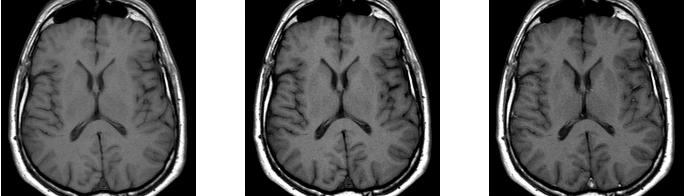

从左到右依次为:

TR 300 ms,翻转 88o \\ TR 550 ms,翻转 70o \\ TR 550 ms,翻转 90o